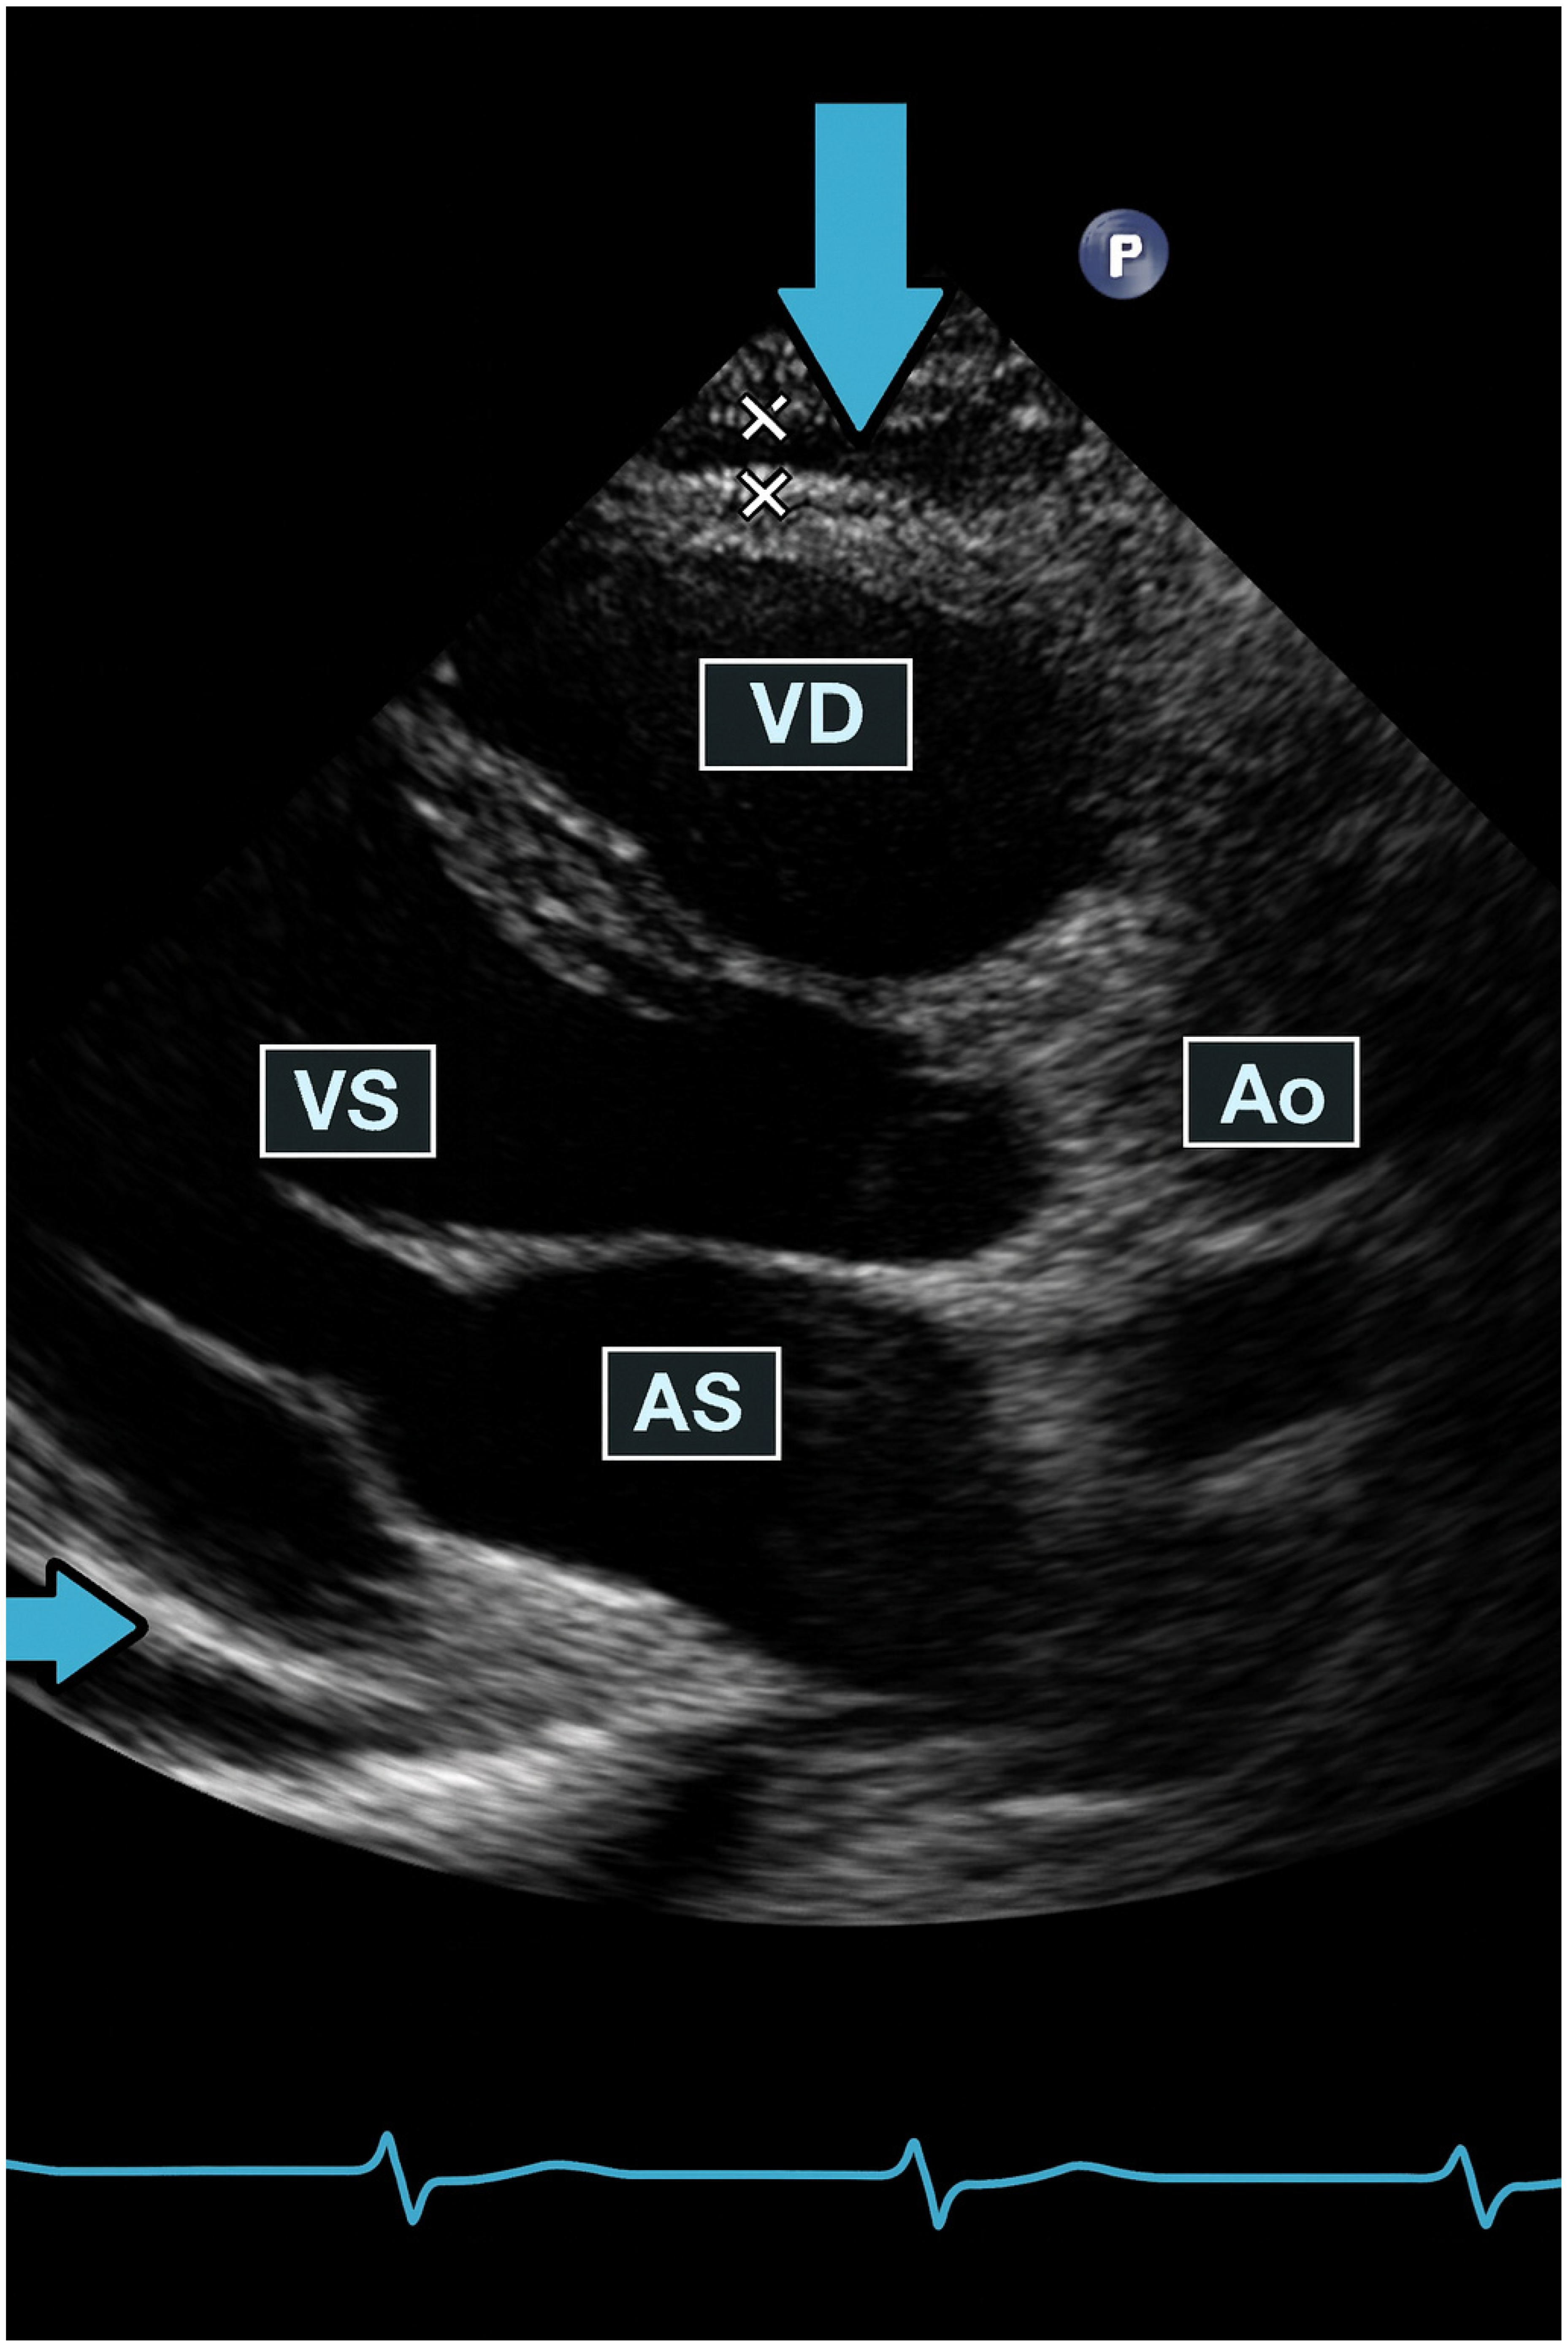

| Pericardial fluid | 0.5 cm | 0.3 cm | ||||||||